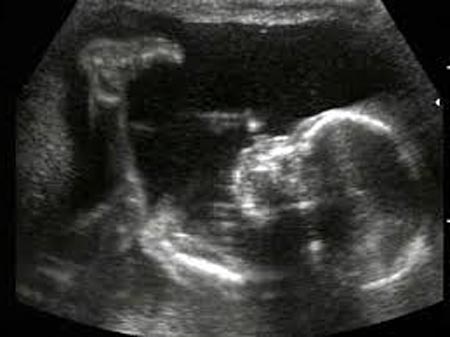

Таким образом, наличие токсикоза, дурной внешности, угрей и высыпаний на коже, выпадения волос и жирной кожи – прямые признаки вынашивания дочери. Фото УЗИ беременности девочкой на 21 неделе можно посмотреть ниже.

Специалисты скажут вам, кого стоит ждать